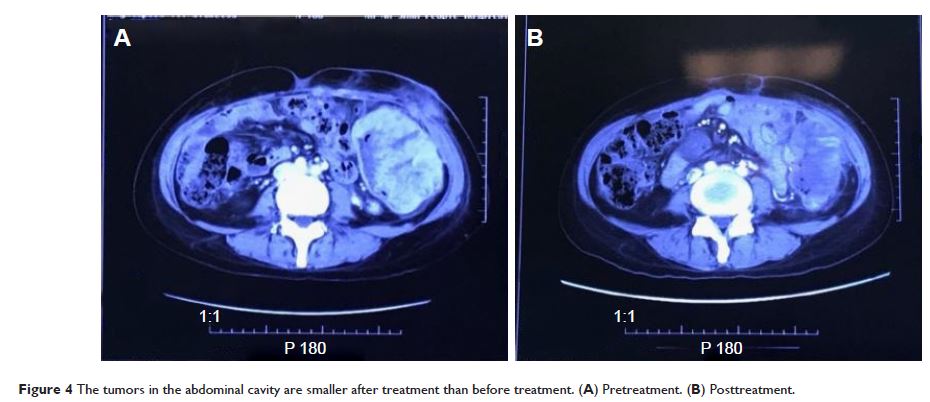

Case Series

- 作者:Yuan Cheng, Juan Zhang, Haiyun Geng, Shukui Qin, Haiqing Hua

- 期刊:OncoTargets and Therapy